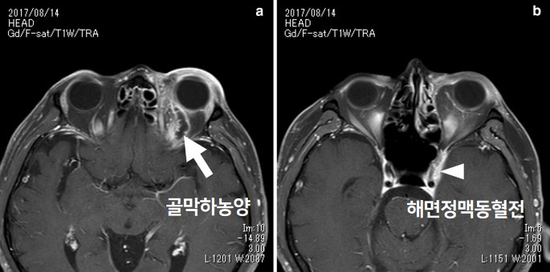

골막하농양(왼쪽)과 해면정맥동 혈전, 안와첨증후군(오른쪽)의 MRI 영상해면정맥동 혈전과 안와첨증후군은 가장 심한 형태의 합병증입니다.해면상 맥동과 안와첨은 2회~6회 뇌신경을 거치기 때문에 급격한 시력 장애, 복시, 안구 운동 장애와 함께 결막 부종, 안구 돌출, 수막 염증상(두통, 한기, 발열)을 수반합니다.